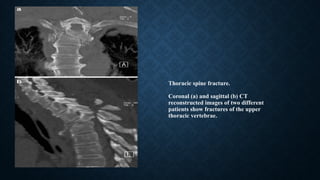

Thoracic spine fracture.

Coronal (a) and sagittal (b) CT

reconstructed images of two different

patients show fractures of the upper

thoracic vertebrae.

SPINE INJURY

• Thoracic spine fractures account for up to 30% of all spine fractures.

• 62% of spine fractures will result in neurological deficits. The most vulnerable site is

between the ninth and twelfth vertebra.

• The main mechanism is hyperflexion and axial loading.

• Sagittal and coronal MDCT reformats readily reveal even small spinal fractures.

• MDCT of the spine is highly indicated for spinal survey for possible fractures and

determine the type of fracture. However, in the case of suspected compressive myelopathy,

MRI is the method of choice.